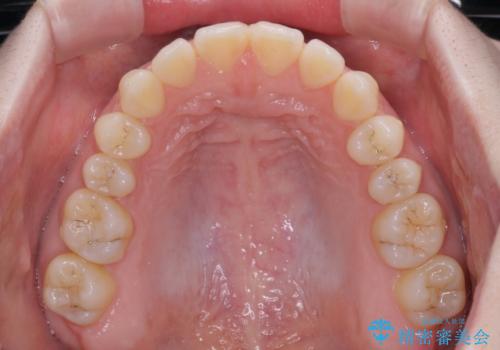

すきっ歯をインビザラインできれいな歯並びに改善

- 1年5ヶ月

- 前歯の隙間を気にして来院された患者様です。

隙間や叢生の程度はそれほど著しいものではなかったので、インビザラインでもワイヤー矯正でも対応可能でしたが、極力目立たない装置を希望されたため、インビザラインにて矯正治療を行うこととしました。